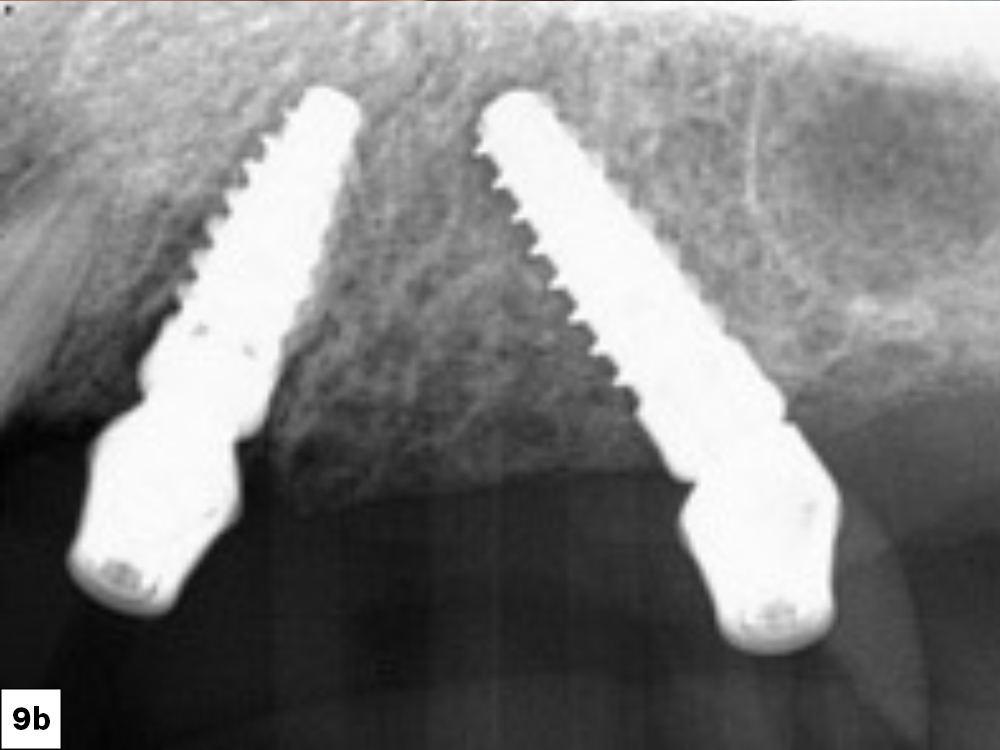

경사 식립으로 골이식 최소화

후방부 치조골이 심하게 흡수된 경우에도 경사 식립(Tilted Implant) 기법을 적용하면 대규모 골이식 없이 전악 수복이 가능합니다. 30~45도로 기울여 식립된 임플란트는 더 넓은 골 표면적을 확보해 초기 고정력(Primary Stability)을 높이고, 이는 수술 당일 또는 수일 내 임시 치아를 장착하는 즉시 하중(Immediate Loading)의 핵심 전제 조건이 됩니다.